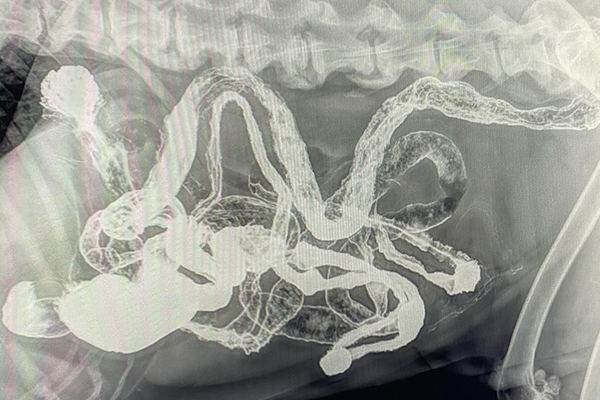

Barium Series

This procedure is a Contrast Study which means that we use a contrast dye that shows up on x-ray and highlights certain structures. Because some objects don’t show up on xray (plastic, fabric, toys, etc), this can help outline it or show us where the obstruction is as it can’t get past.

Our talented Registered Veterinary Technicians administer barium (the contrast liquid) in the mouth and then we take successive X-rays over the next few hours to watch its progress. The first X-ray is almost immediate to catch the outline of the esophagus while the last one may be hours later as it enters the colon .

Flip through the photos to see the progression of barium through the gastrointestinal tract: